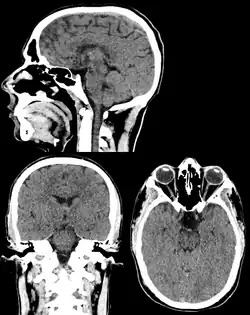

Head & Neck Imaging

CT scan remains the cornerstone imaging modality for the initial evaluation and subsequent management of patients with acute traumatic brain injury due to its rapid acquisition time and high sensitivity for detecting hemorrhagic complications, such as intraparenchymal hematomas and subdural hemorrhages.[56] CT scan of the head is typically used to detect infarction (stroke), tumors, calcifications, haemorrhage.[57] Tumors can be detected by the swelling and anatomical distortion they cause, or by surrounding edema. CT scanning of the head is also used in CT-guided stereotactic surgery and radiosurgery for treatment of intracranial tumors, arteriovenous malformations, and other surgically treatable conditions using a device known as the N-localizer.[58][59][60][61][62][63]

Contrast CT is generally the initial study of choice for neck masses in adults.[64] CT of the thyroid plays an important role in the evaluation of thyroid cancer.[65] CT scan often incidentally finds thyroid abnormalities, and so is often the preferred investigation modality for thyroid abnormalities.[65]